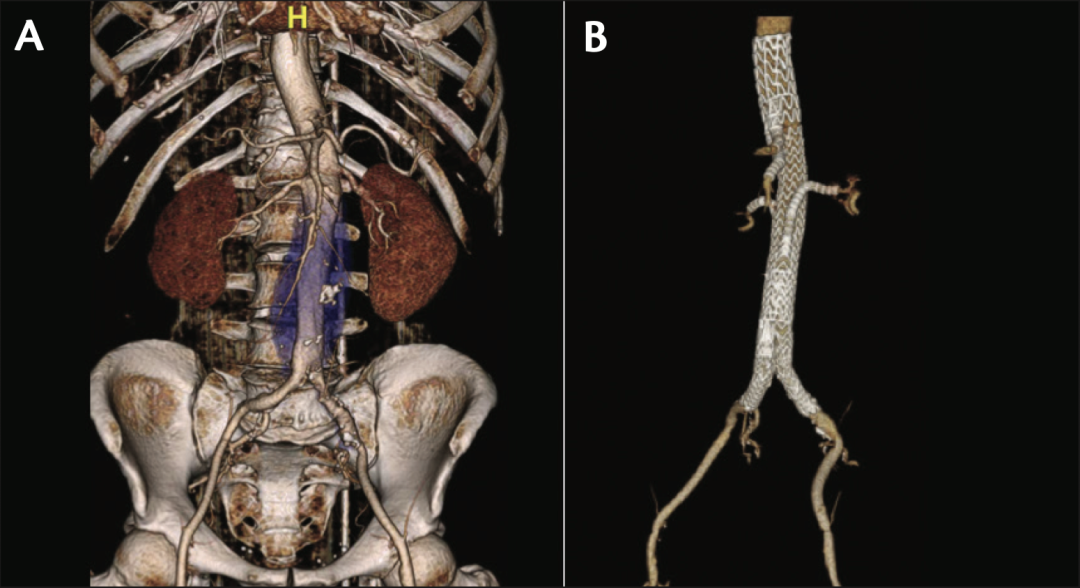

巴西弗洛里亚诺波利斯首例全球手术(由圣卡塔琳娜联邦大学的Pierre Galvagni医生及其团队完成)。术前(A)与术后(B)CTA显示支架移植物通畅良好,术后1年无内漏。

巴西弗洛里亚诺波利斯第二例全球手术(由圣卡塔琳娜联邦大学的Pierre Galvagni医生及其团队完成)。术前(A)与术后(B)CTA显示支架移植物通畅良好,术后1年无内漏。